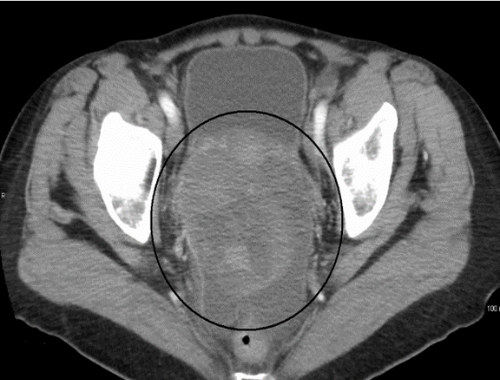

Tomografía de cáncer de ovario

Cáncer epitelial de ovario